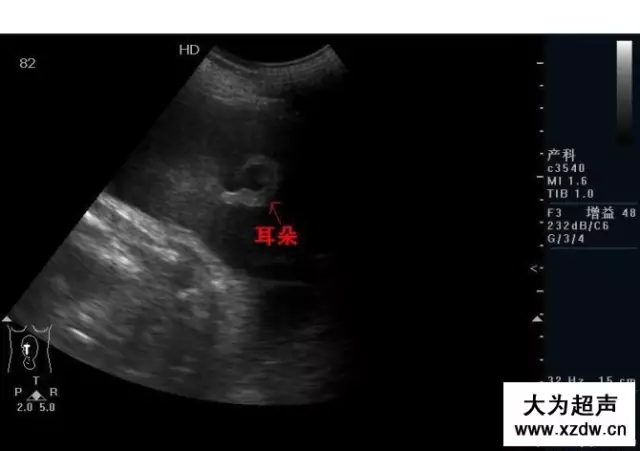

產(chǎn)科超聲正常圖片